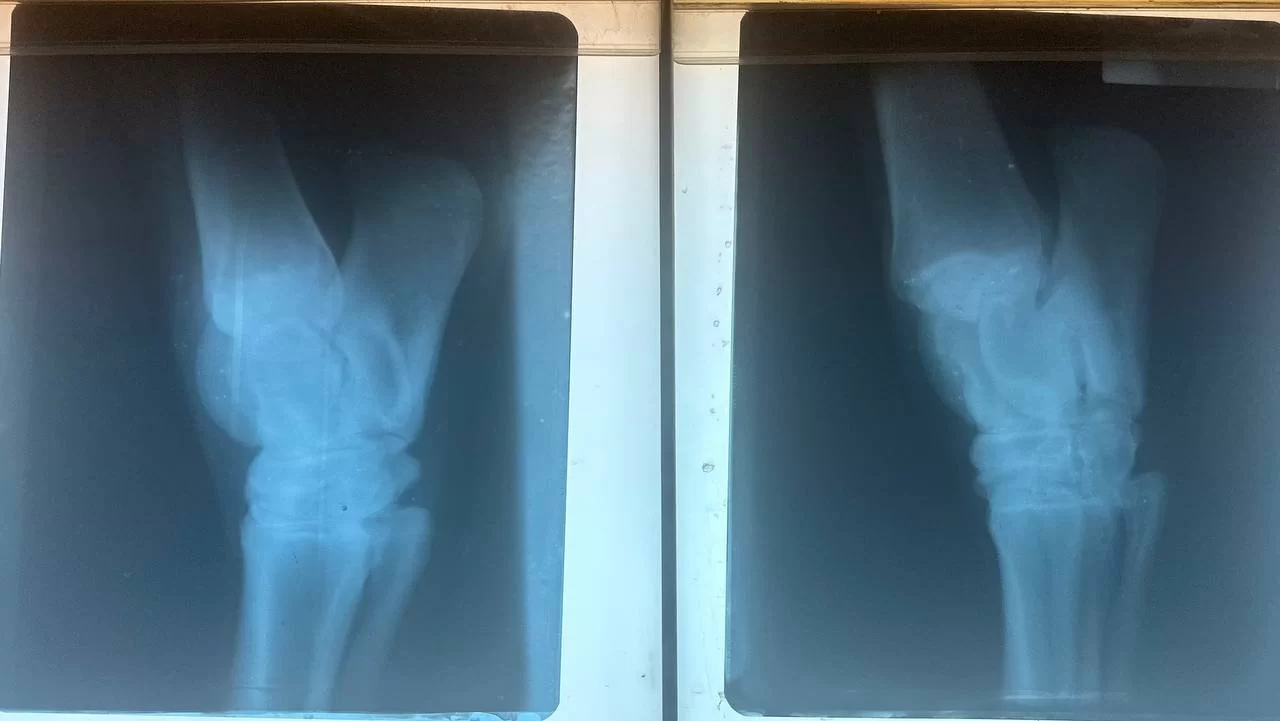

إستقبل المستشفى التعليمي البيطري بجامعة طرابلس اليوم حالة مرضية لحصان يعاني من العرج بالقائمة الخلفية اليسرى.

حيث أجريت له الكشوفات اللازمة من قبل أساتذة الجراحة والتخدير والأشعة. هذا وقد تم تأكيد الحالة بإجراء الأشعة التشخيصية السينية، ومن ثم وصف العلاج اللازم له.